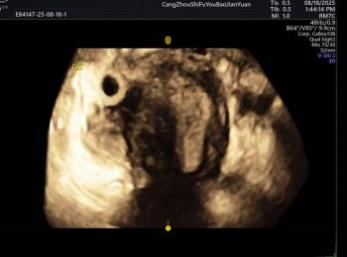

给宝宝的“立体影像”,让产检更安心

科室采用三维/四维超声技术开展胎儿检查,能清晰呈现胎儿面部及身体关键结构的影像,让准父母直观感受宝宝的发育状态。检查中,医生会借助技术对唇腭裂、小下颌等结构异常进行细致观察,同时基于三维容积数据,从多个平面评估胎儿心脏、大脑、脊柱等重要部位,为孕期健康管理提供专业参考。

正常胎儿面部三维照片

四维诊断小下颌畸形